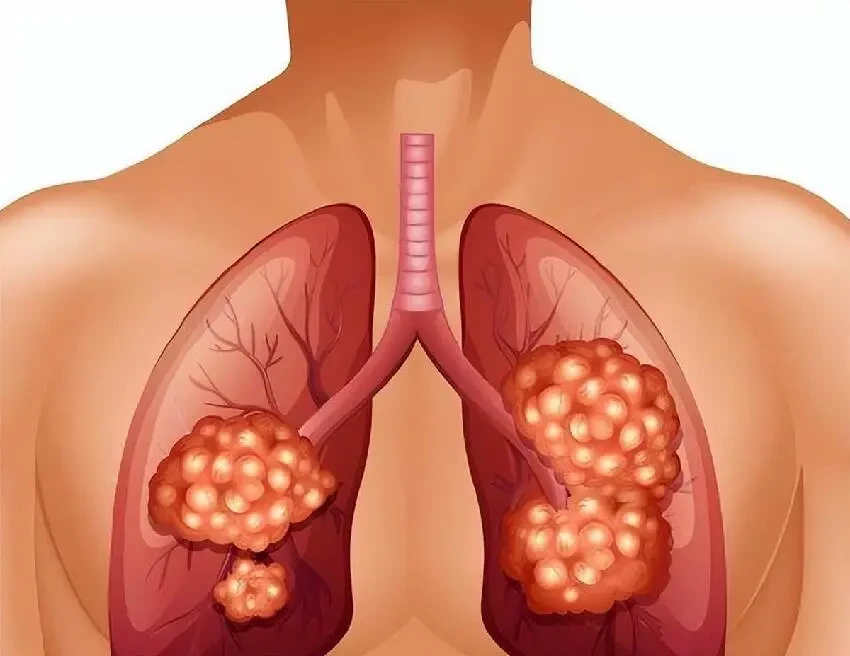

當肺癌發展到一定階段,腫瘤就像一個逐漸膨脹的氣球,開始壓迫喉嚨部位的神經和組織。

這時候,患者吞咽食物就會變得不順暢,就好像有什麼東西卡在了嗓子眼,每咽一口都特別費勁。

同時,腫瘤還可能壓迫到聲帶,讓聲音變得沙啞。

肺癌的早期症狀和腫瘤的大小、位置關係密切。

比如,長在肺尖的腫瘤,就像一顆隱藏在角落裡的定時炸彈,它常常會 「騷擾」 喉部和吞咽相關的部位,讓患者出現喉嚨不舒服、吞咽困難等症狀,而這些症狀又特別容易和咽喉炎、普通咳嗽混淆。